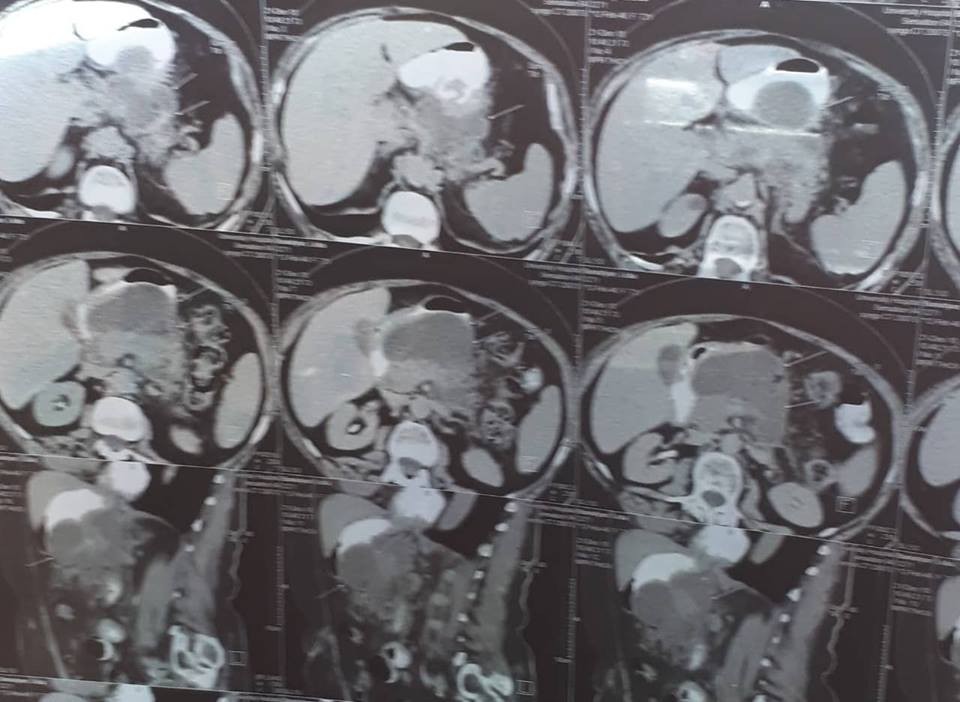

տղամարդը եւ հիպերտենզիա ԱՓՇ-ում…Այս խնդիրների դեպքում բաց վիրահատությունը ուղղակի հակացուցված է: Արա Վարդանյանը ընտրել է այլ ճանապարհ: Առաջին հերթին՝ տեղային անզգայացման պայմաններումուլտրաձայնայինհսկողությամբ իրականացվել է հետորովայնամզային տարածության թարախակույտի դրենավորում, հաջորդ օրը կատարվել է ճարպոնային ծոցի դրենավորում: Սահմանվել է դինամիկ հսկողություն եւ կոնսերվատիվ թերապիա: Ինֆուզիոն, հակաբակտերիալ, սիմպտոմատիկ թերապիան շարունակվել է վիրաբուժական բաժանմունքում: Սրանով, սակայն, բուժումը չի ավարտվել: Մի քանի օր անց դրենավորվել է նաեւ աջից ենթադիաֆրագմալ տարածությունում առկա թարախակույտը: Հիվանդը ստոցիոնարում բուժումը շարունակել է եւս մի քանի օր եւ դուրս գրվել հիվանդանոցից բավարար վիճակում, ճարպոնային ծոցի եւ հետորովայնամզային տարածության գործող դրենաժներով: Նա, իհարկե, կշարունակի մնալբժշկի հսկողության տակ, բայց վերադարձել է նախկին կենսակերպին, ցավային զգացողություններ չունի: